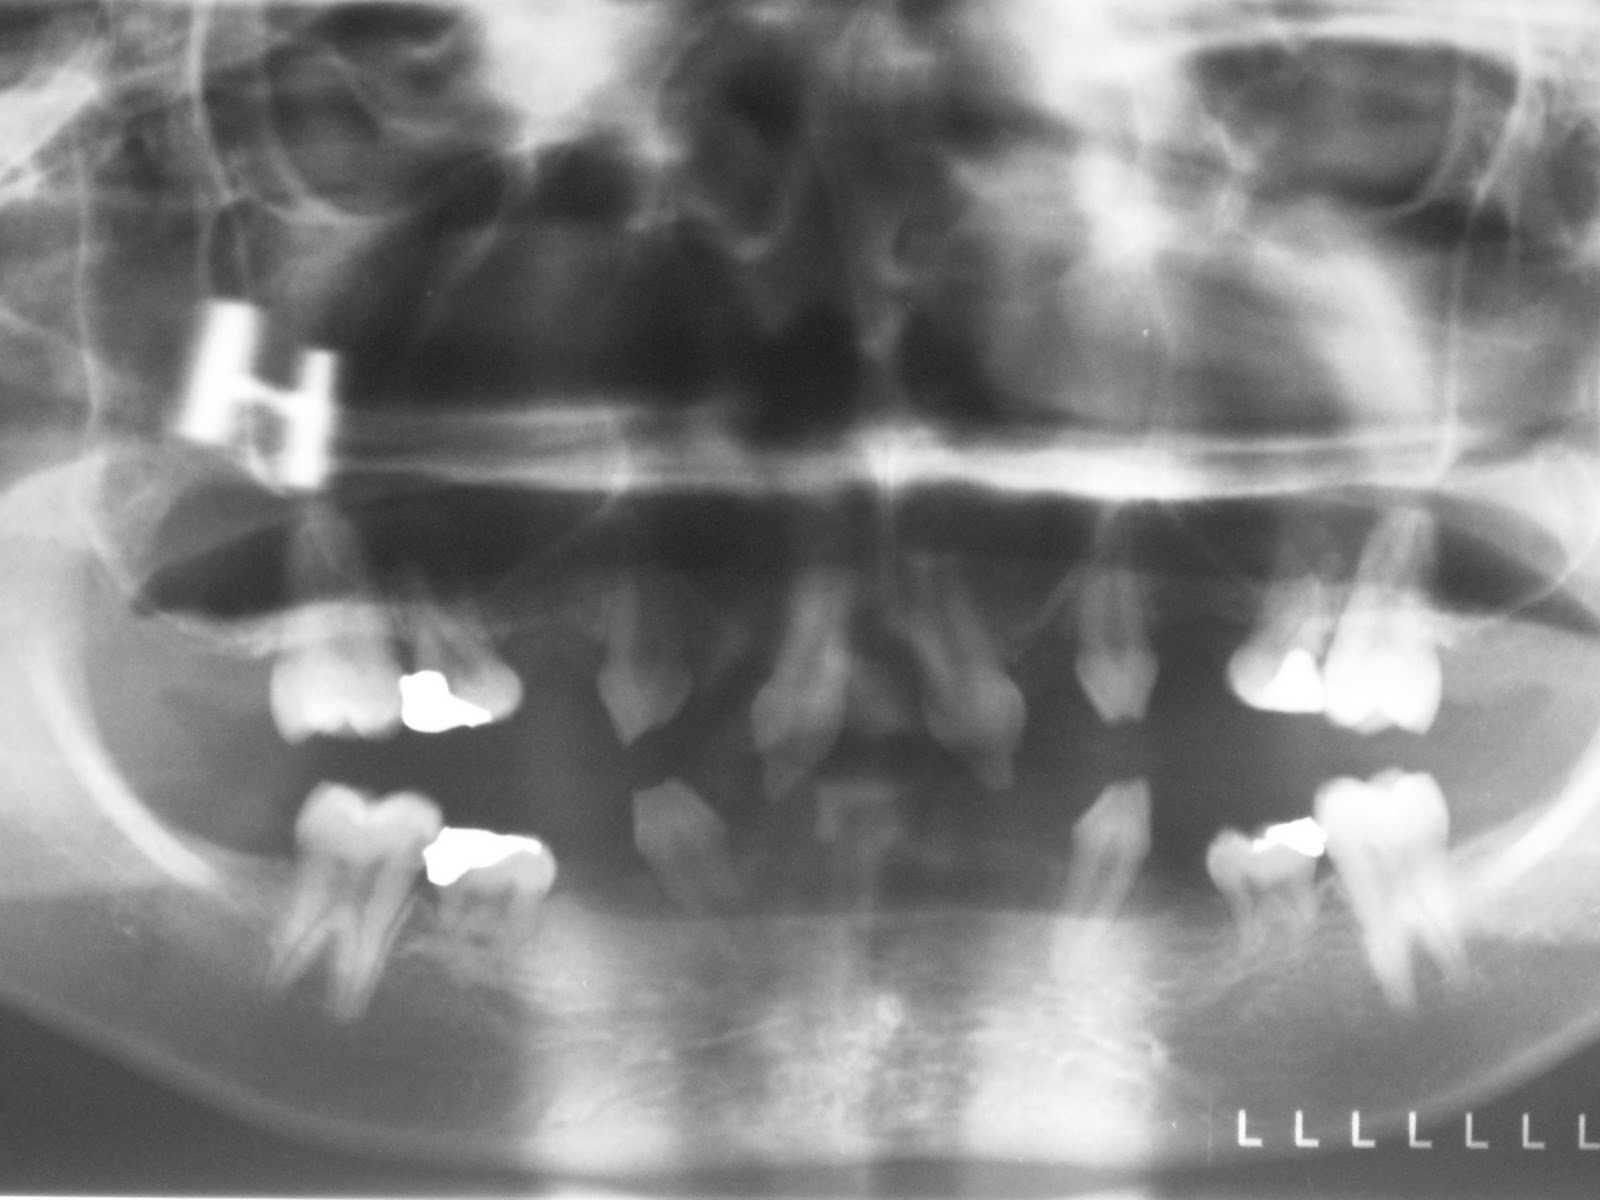

Below is the orthopaedic appliance.

It is an attempt to bodily move the two canines forward together with its supporting alveolar bone so as to improve the overbite/overjet relationship with the uppers.

As you can see, it succeeded quite admirably.